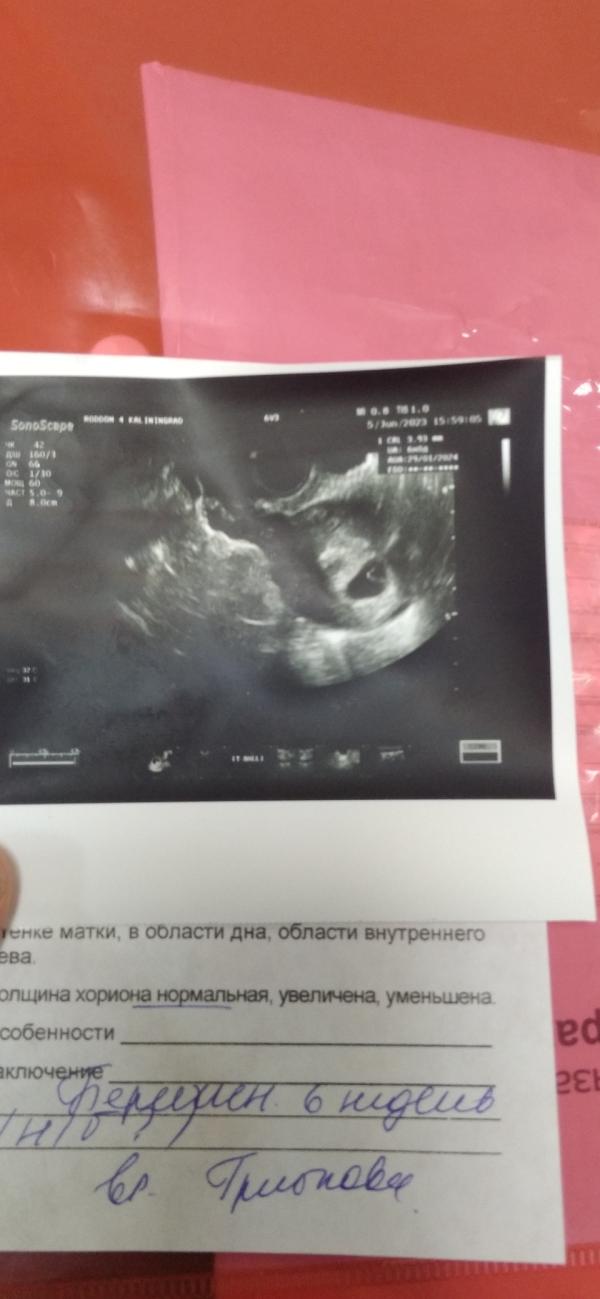

Сходила на узи теперь повторное 13 числа .. Сказала еще сердце не бьётся нужно смотреть 13 .. Переживаю капец . по месячным уже срок 9 недель. По узи 6 .. На учет еще не ставят сказала после контрольного узи что бы все хорошо было .. Переживаю ппц как . надеялась уже сегодня увижу больше плод ..